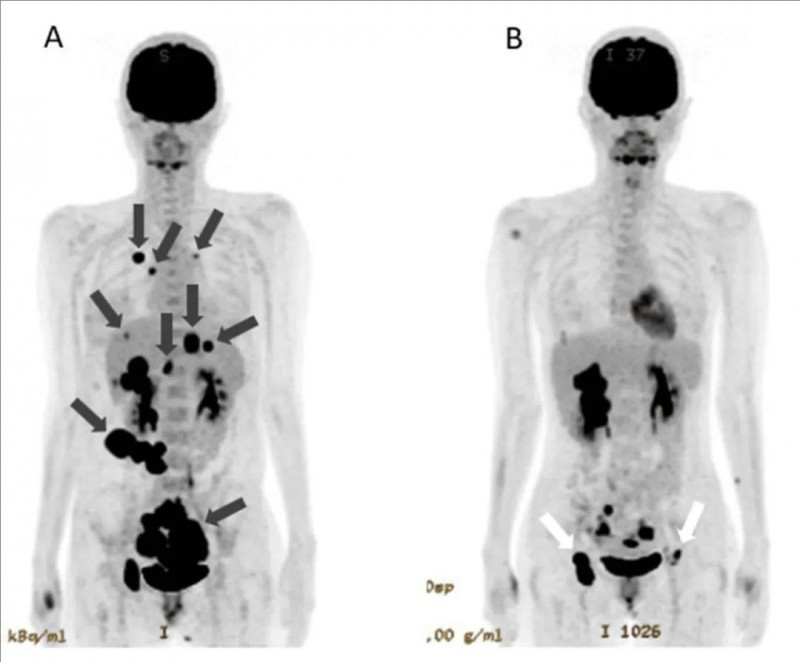

本例患者是一位30岁左右的女性,生下二胎6个月后,突然出现腹水。确诊为IV期子宫内膜癌(图1A)。全身PET-CT提示伴全身转移,包括双侧卵巢癌、腹膜播散、肝多发转移、骨转移、肺转移。确诊当天腹部CT扫描提示大量腹水(图2A)。患者按常规治疗方案开始仅进行化疗,但医生判断预后不佳,遂开始同时进行免疫细胞治疗。经过化疗(紫杉醇+卡铂AUC5)+多轮WT1(是一种常见的癌症抗原,在各种类型的癌症中均有高表达)-DC(树突状细胞疫苗疗法)+高活性NK细胞治疗后,结果显示如下:

1、肿瘤体积明显缩小:治疗前PET-CT显示,该患者存在原发性卵巢癌病灶,以及肝脏、肺部、腹膜等多处转移灶(详见图1A)。NK细胞+WT1-DC疫苗+纳武单抗联合治疗第142天,PET-CT显示原发性肿瘤明显缩小,肺转移灶及腹膜播散灶消失,肝转移灶明显缩小(详见图1B)。由于肿瘤明显缩小,患者计划考虑进行原发肿瘤根治性切除术。

图1 该患者治疗前后PET-CT对比

▲图源“Cureus”,版权归原作者所有,如无意中侵犯了知识产权,请联系我们删除

注:

①图1A(治疗前PET-CT):可见原发性卵巢癌,以及肝脏、腹膜、肺等多处转移灶(黑色箭头)。

②图1B(治疗第142天PET-CT):显示原发性肿瘤明显缩小,肺转移灶及腹膜播散灶消失,肝转移灶缩小。白色箭头-表示腹股沟区接种树突状细胞疫苗后出现的炎症反应。